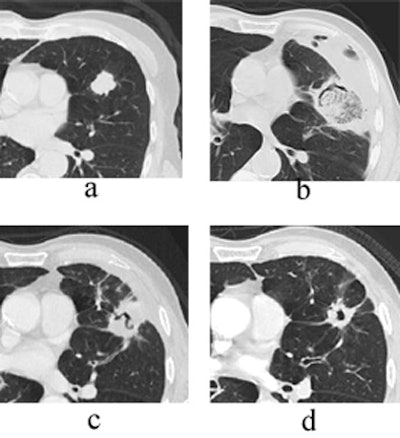

"Here you see the appearance of a treated lesion of the 12-month study period, as well as lesion enhancement values at the respective time points," Wallace said. "The ablated zone lesion initially appears larger, likely due to local inflammation. The lesion eventually becomes cavitary, and ultimately takes on the appearance of what looks like a scar on CT."

![]() |

| Transverse thin-section CT of a lingular segment nodule prior to RFA and one, three, and six months after RFA. (a) Baseline scan obtained prior to RFA shows a 2.2 x 2.8-cm nodule. (b) Scan one month after RFA shows marked interval increase in nodule size with early formation of a thick-walled cavity and adjacent anterolateral complicated hydropneumothorax. (c) Scan three months after RFA demonstrates interval regression of cavitary lesion and resolving adjacent hydropneumothorax. (d) Scan six months after RFA shows further interval regression of cavitary lesion and resolved hydropneumothorax. Images courtesy of Drs. Robert Suh, Jonathan Goldin, and Amanda Wallace, UCLA School of Medicine, Los Angeles. |